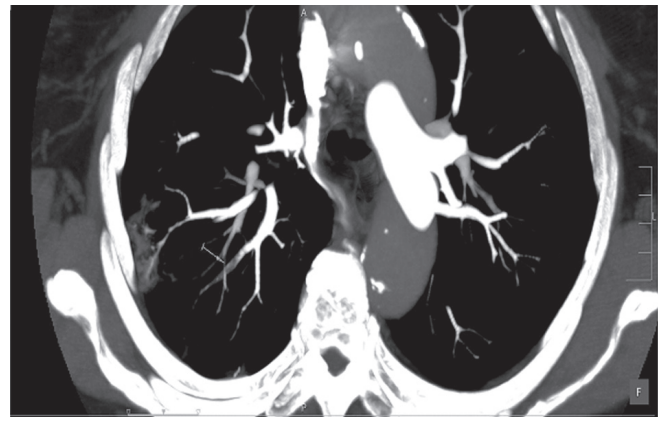

El foramen oval permeable (FOP) es un defecto del septum interauricular que puede coexistir con aneurisma de éste y se asocia con pasaje de flujo de izquierda a derecha. Su presencia se ha vinculado con accidente cerebrovascular (ACV) embólico y con el síndrome de platipnea-ortodesoxia. En esta presentación se describe el caso de una paciente con síndrome de platipnea-ortodesoxia que representó un verdadero desafío diagnóstico, ya que ingresó a nuestra institución por neumonía y luego incidentalmente se diagnosticó una tromboembolia de pulmón (TEP). Dada la tórpida evolución y al evidenciarse disnea con desaturación que se acentuaba al sentarse, se realizó un ecocardiograma transesofágico (ETE) que mostró un FOP con aneurisma del septum interauricular y pasaje marcado de burbujas de derecha a izquierda en forma espontánea (en decúbito dorsal). Luego de completar tratamiento antibiótico, se procedió al cierre percutáneo del FOP con la colocación de un Amplatzer.